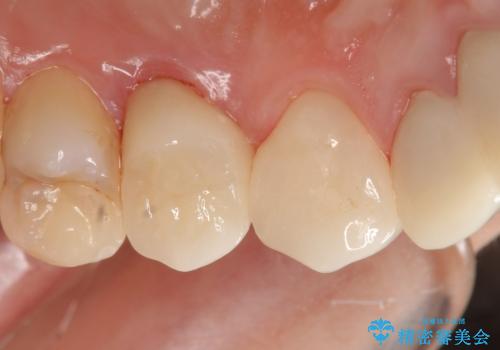

オールセラミッククラウン 歯牙の挺出後の補綴

挺出終了後は歯肉切除および骨外科により歯周組織を整え、オールセラミッククラウンによる補綴を行いました。

オールセラミッククラウン(エコノミー)について

オールセラミッククラウン(エコノミー)はスタンダード以上と違い、一塊となっているため欠けてしまうリスクが低いのが特徴です。

しかしその反面選択できる色の種類が少なく、色合いも単調であるという欠点もありますが、今回のケースのように前後の歯がクラウンの場合などでは十分に審美的な補綴が可能となります。